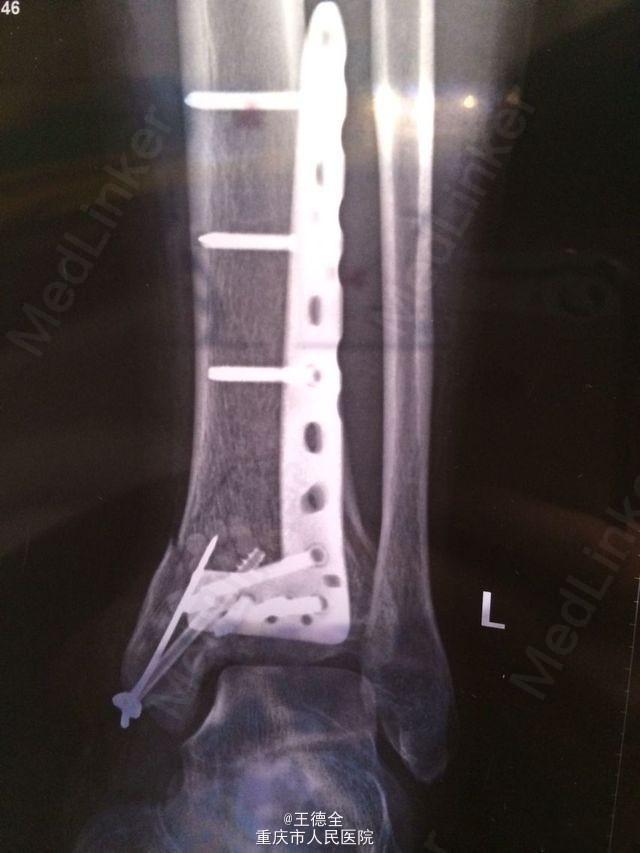

左脚pilon骨折一例

患者老年男性,高出摔落伤,查体:左踝部中度肿胀,畸形,压痛,活动受限,足背动脉波动好,足趾运动及末梢血运、感觉正常。